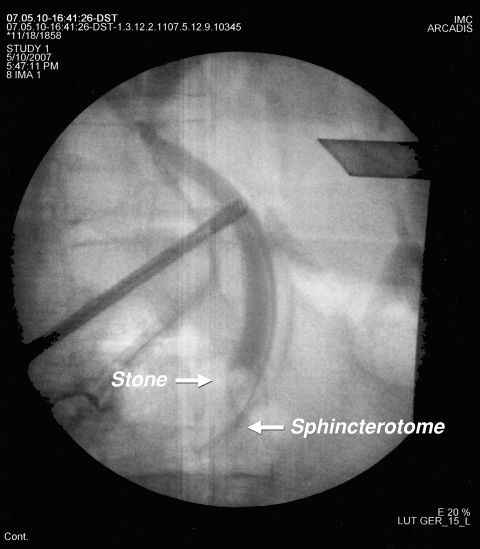

Tek aşamalı işlemin şematik görünümü

Tek aşamalı işlemin radyolojik görünümü